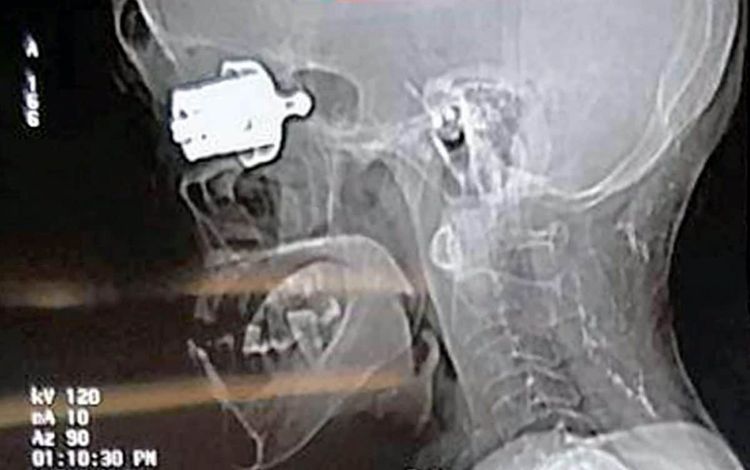

Medics couldn’t see the bullet-sized bit of metal from the outside, but surgeons were able to gently pull it out.

The metallic whistle, around 70mm in length and 20mm wide, was stuck in such a way that it was not visible from outside.

Only a CT scan revealed it was deeply jammed near her brain.